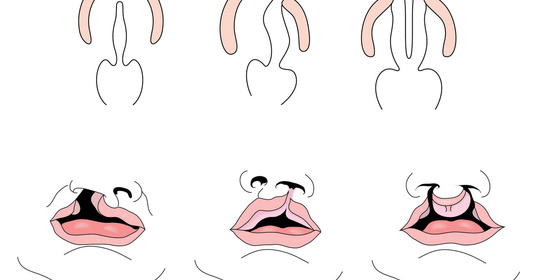

兔唇:瞭解成因、預防與治療,守護寶寶健康成長